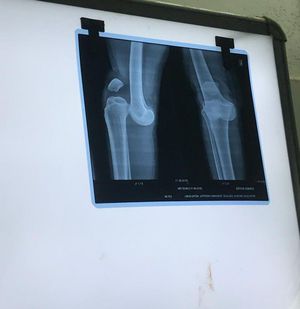

Case of posterior type Knee dislocation due to carrying heavy load All the ligaments are torn Treatment: traction and fitting Recovery:by fibrosis Procedure: tell one person to hold popliteal fossa and traction of the leg which balances the femur to tibia and patella Complications: 30% amputation chance due to rupture of poplitial artery 35% chance of peroneal nerve damage And other many more.

@Rupak dislocation and fracture is not the same thing, the knee joint dislocation is obvious but i can't see the fracture(discontinuity in a bone ) as the heading of the post says π€